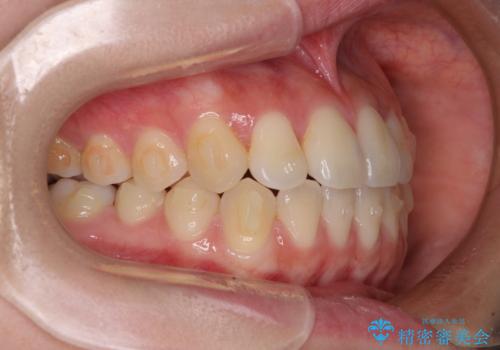

- 前歯のクロスバイトが気になり、インビザラインによる矯正治療を希望して来院された患者様です。

上顎側切歯(上の真ん中から2番目の歯)が舌側転位している場合、インビザラインでは仕上げきれないことが多く、更には無理して動かそうとすると歯髄壊死を起こすリスクが高いと言われています。

インビザラインで歯列を移動する前に、上顎前歯をワイヤー矯正で整え、その後上下歯列をインビザラインにて矯正治療を行うこととしました。

舌側転位している側切歯特有の、切縁の位置が不揃いであったり、根元が内側に引っ込んだ状態であったりという、インビザライン独特の仕上がりになることなく、きれいに整った歯列とすることができました。